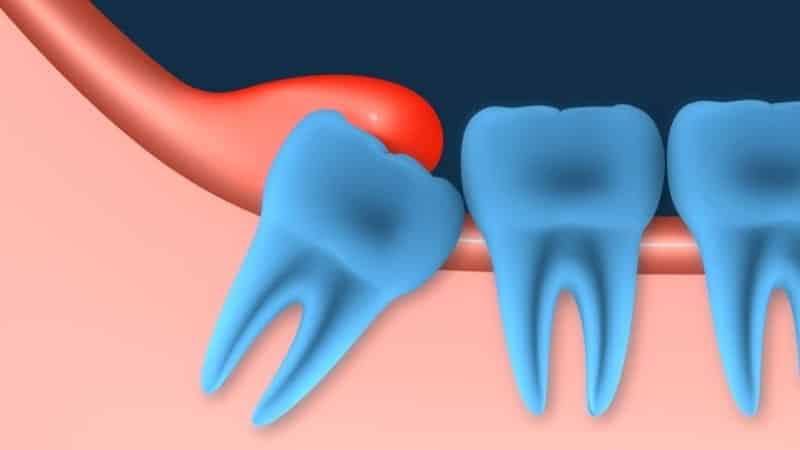

Во время роста зуба мудрости у людей часто возникают осложнения, связанные с воспалительными процессами в десне. На поверхности десны появляется бугорковое образование, покрытое слизистой оболочкой. Это место подвержено травмам и механическим повреждениям от твердой пищи, что способствует развитию вредных микроорганизмов, бактерий и нагноений.

Такие образования являются признаком перикоронарита — заболевания, которое начинается с незначительных болевых ощущений в области роста зуба мудрости. С развитием воспаления боль становится сильнее и может распространяться в виски, уши и при глотании. Возможны также боли в лицевых мышцах, воспаление тройничного нерва, лимфатических узлов, а иногда даже повышение температуры и головная боль. Образование капюшона сопровождается отечностью и покраснением, а также выделением гноя.

- Ретинированный зуб мудрости, который не может прорезаться из-за неправильного расположения в челюсти и упора в соседние зубы.

- Частичное прорезывание, вызывающее воспалительные процессы и боль.